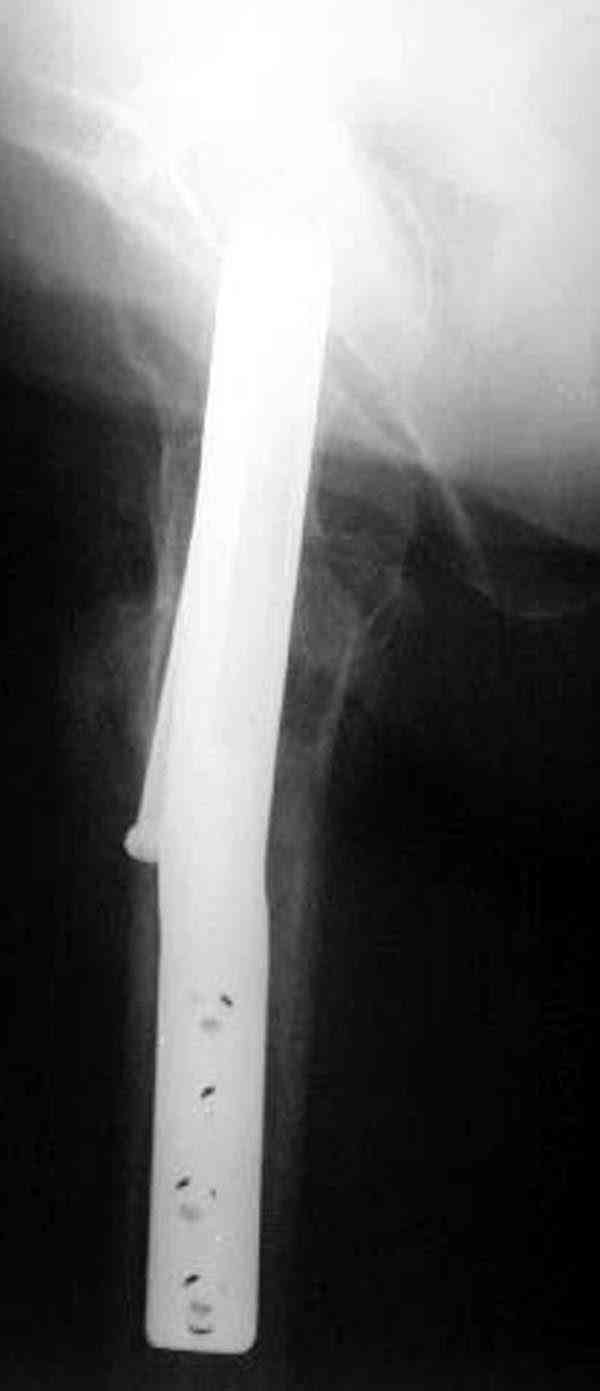

Кстати говоря, ослабление латерального кортекса винтом может способствовать возникновению вертельного и подвертельного перелома.

Коллега Челноков прав, здесь еще имеется риск перелома за счет ослабления латерального кортекса. Во время установки канюлированных шурупов за редким исключением спица вводится с одного раза, множественные попытки ослабляют латеральный кортекс, что станет источником перелома в этом месте.

Здесь случай перелома из-за ослабления латерального кортекса через 3 недели после операции на шейке. Шурупы были установлены под большим углом, слабый латеральный кортекс не выдержал нагрузку.